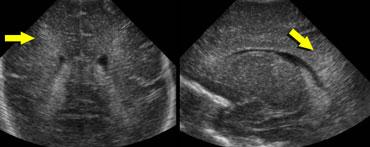

Flaring

Thuật ngữ flaring được dùng để mô tả các vùng quanh não thất có hồi âm tăng nhẹ, thường gặp ở nhiều trẻ sinh non trong tuần đầu tiên của cuộc đời.

Trong tuần đầu này, chưa thể xác định chắc chắn đây là biến thể bình thường hay là dấu hiệu của PVL độ 1.

Flaring tồn tại kéo dài sau tuần đầu tiên của cuộc đời được định nghĩa là PVL độ 1.

TRÁI: Hình ảnh khảo sát ban đầu cho thấy flaring. PHẢI: Hình ảnh tái khám sau một tuần cho thấy chất trắng quanh não thất bình thường.

Cần theo dõi tái khám để phân biệt flaring với PVL độ I.

Trường hợp bên trái minh họa một trẻ sinh non có hình ảnh flaring.

Tại lần tái khám, không ghi nhận sự hình thành nang và sau tuần đầu tiên, chất trắng quanh não thất trở về hình ảnh bình thường.